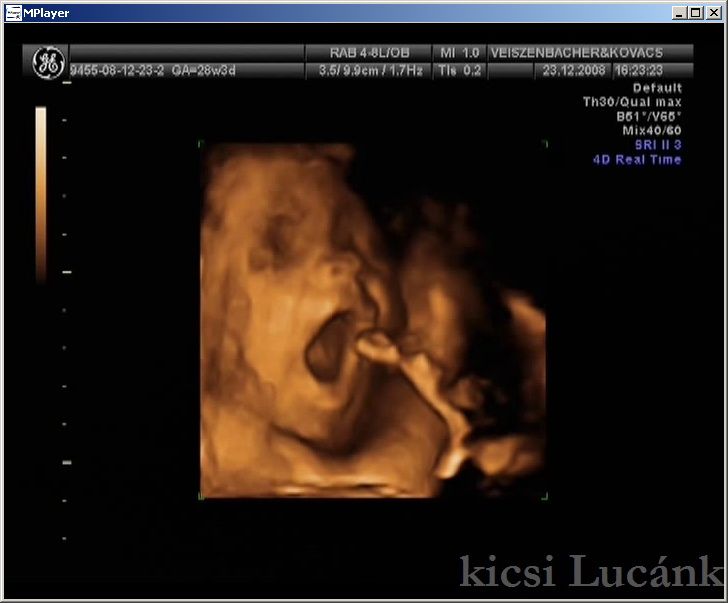

kicsi Lucánk - 2008.12.23 (12 of 13)

luca12